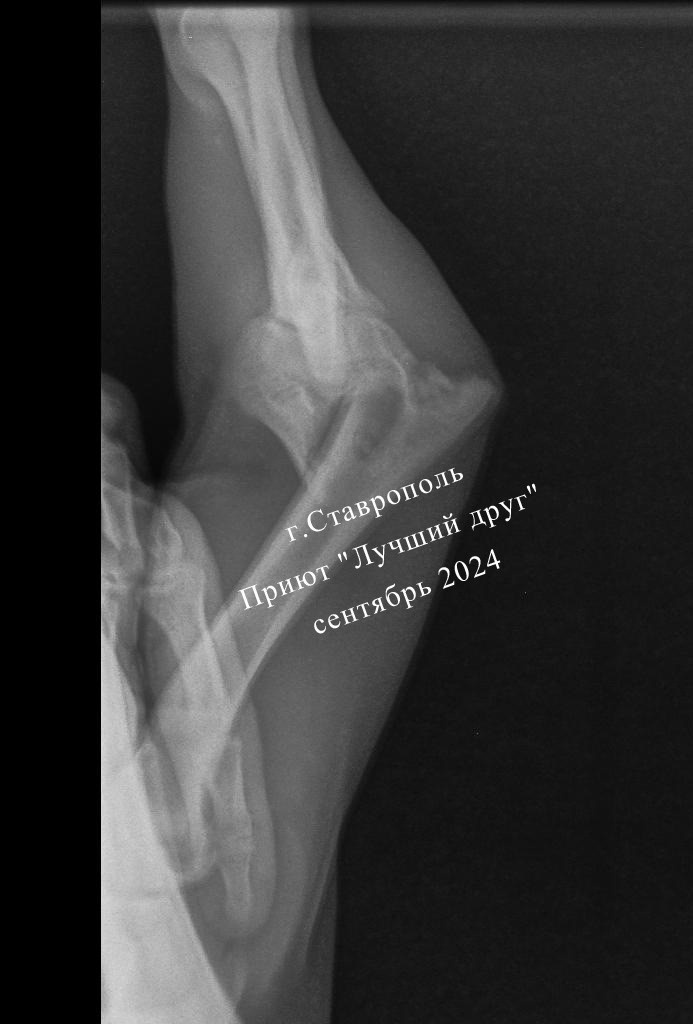

Пса Везунчика выписали из клиники в приют. На стационаре ему стабилизировали состояние, пироплазмоз пролечили, максимально подготовили к операции на лапе. Но перелом очень сложный, мелкие обломки разлетелись и собирать их будут в другой клинике через некоторое время. На стационаре Везунчика лечили в долг, его нужно будет обязательно оплатить. И необходимо срочно собрать примерно 18 тысяч на операцию, в долг оперировать не будут, увы... Пса привезли в клинику в тяжелом состоянии. Перелом левой передней лапы, неврологический дефицит правой передней лапы, контузия грудной клетки, всё тело в ссадинах, и, как вишенка на торте, запущенный пироплазмоз... Беднягу назвали Везунчиком, ему действительно повезло, что его заметила девушка-волонтер и отвезла в клинику. Но, как это часто бывает, у неравнодушных людей слишком много подопечных и слишком мало денег для спасения очередного горемыки, поэтому куратор попросила помощь в приюте, в том числе и в оплате счетов за спасение пёсика.

Пса привезли в клинику в тяжелом состоянии. Перелом левой передней лапы, неврологический дефицит правой передней лапы, контузия грудной клетки, всё тело в ссадинах, и, как вишенка на торте, запущенный пироплазмоз...